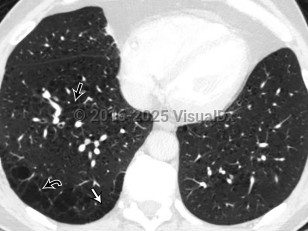

Pulmonary emphysema

Pulmonary emphysema is a type of chronic obstructive pulmonary disease (COPD) characterized by the loss of individual alveolar wall structures, resulting in larger and less efficient alveoli with air trapping. Shortness of breath begins gradually; it may take years for affected patients to seek treatment. Other findings include wheezing, cough, chest pain, cyanosis, and increased heart rate.

Emphysema is a chronic medical condition. While pharmacologic and lifestyle changes may improve symptoms, in general, patients have a gradual increase in symptoms and burden of disease with time. The primary cause is smoking and/or inhalation of other pollutants. Pulmonary emphysema can also be secondary to alpha-1 antitrypsin deficiency, which leads to unopposed elastase activity in the lung. Treatments include lifestyle changes, supplemental oxygen, medications, and possibly surgery.